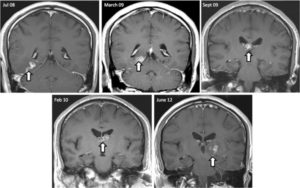

mri

病理